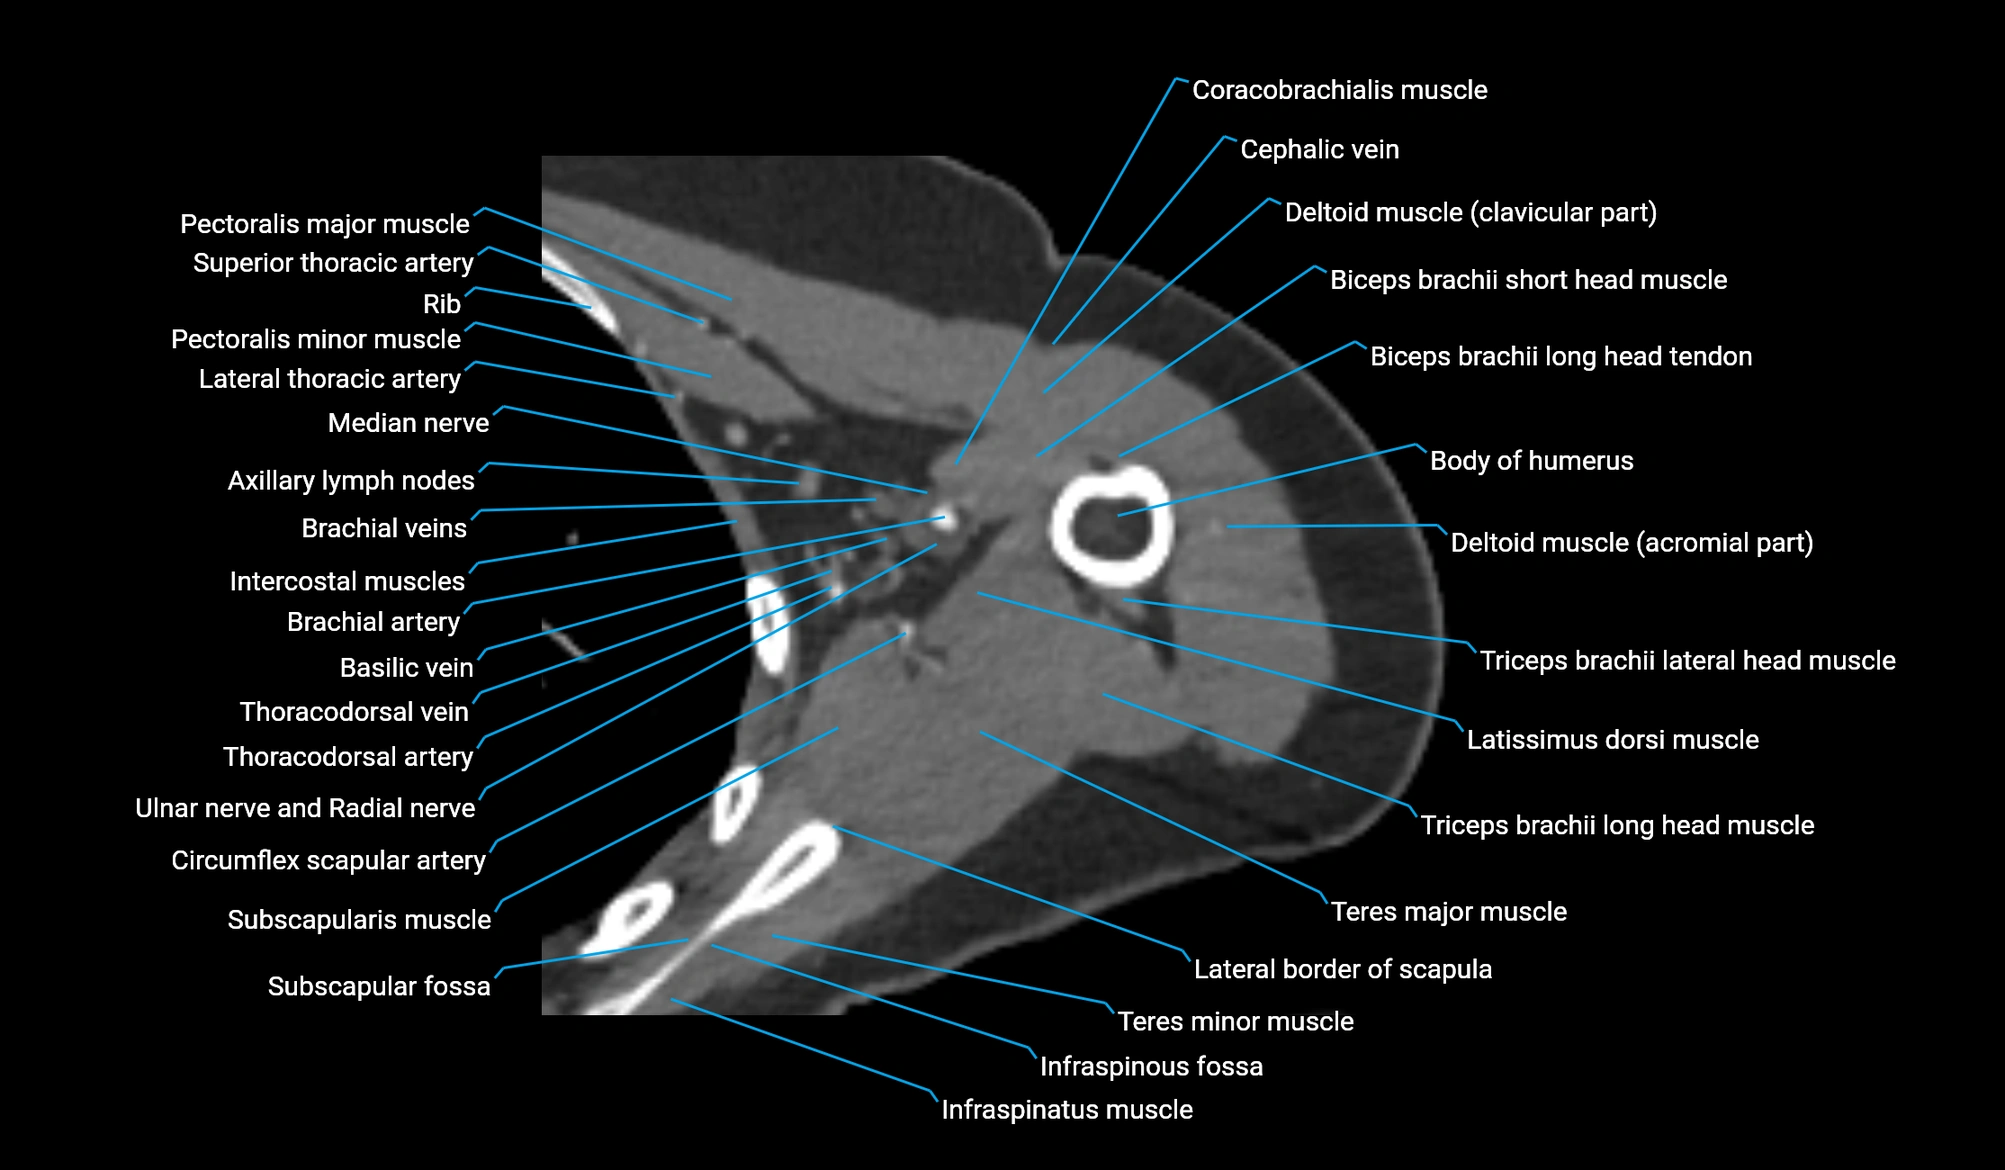

CT image